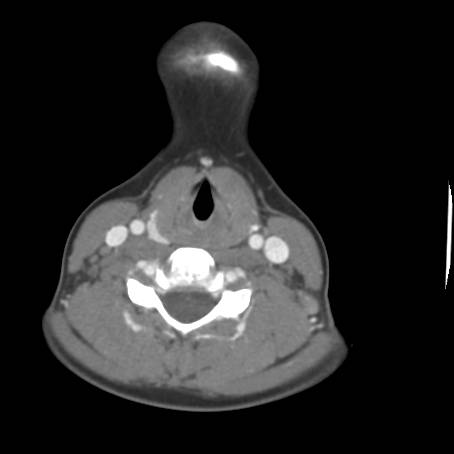

![]() Figure 5c |

Describe CT.